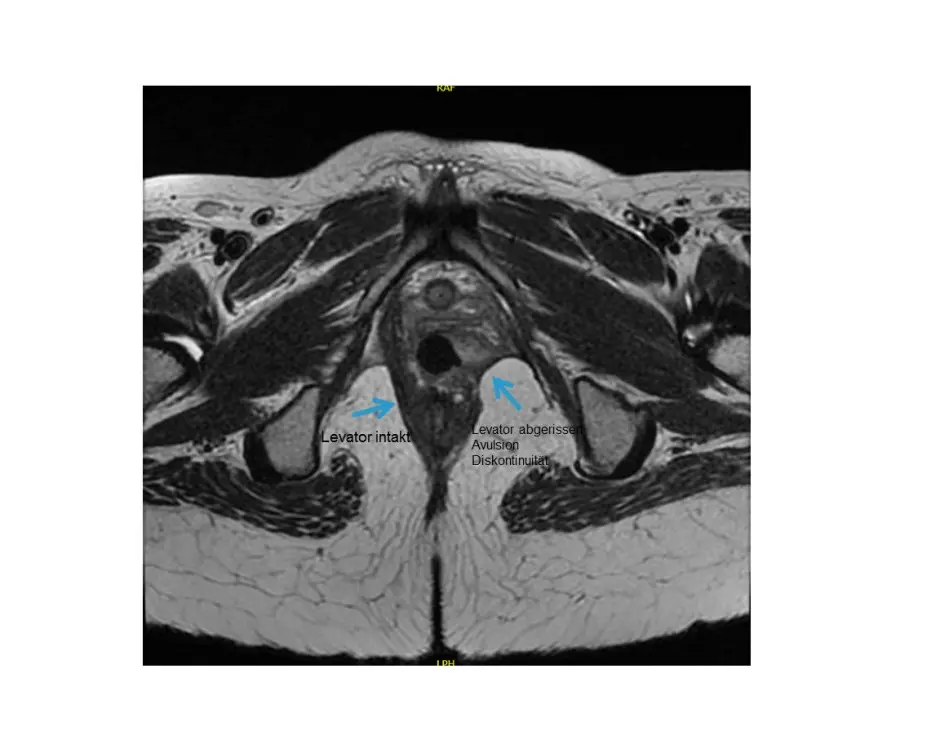

- Magnetresonanztomographie (MRT): Diese Untersuchung kann zur Beurteilung der Struktur des Beckenbodens eingesetzt werden.